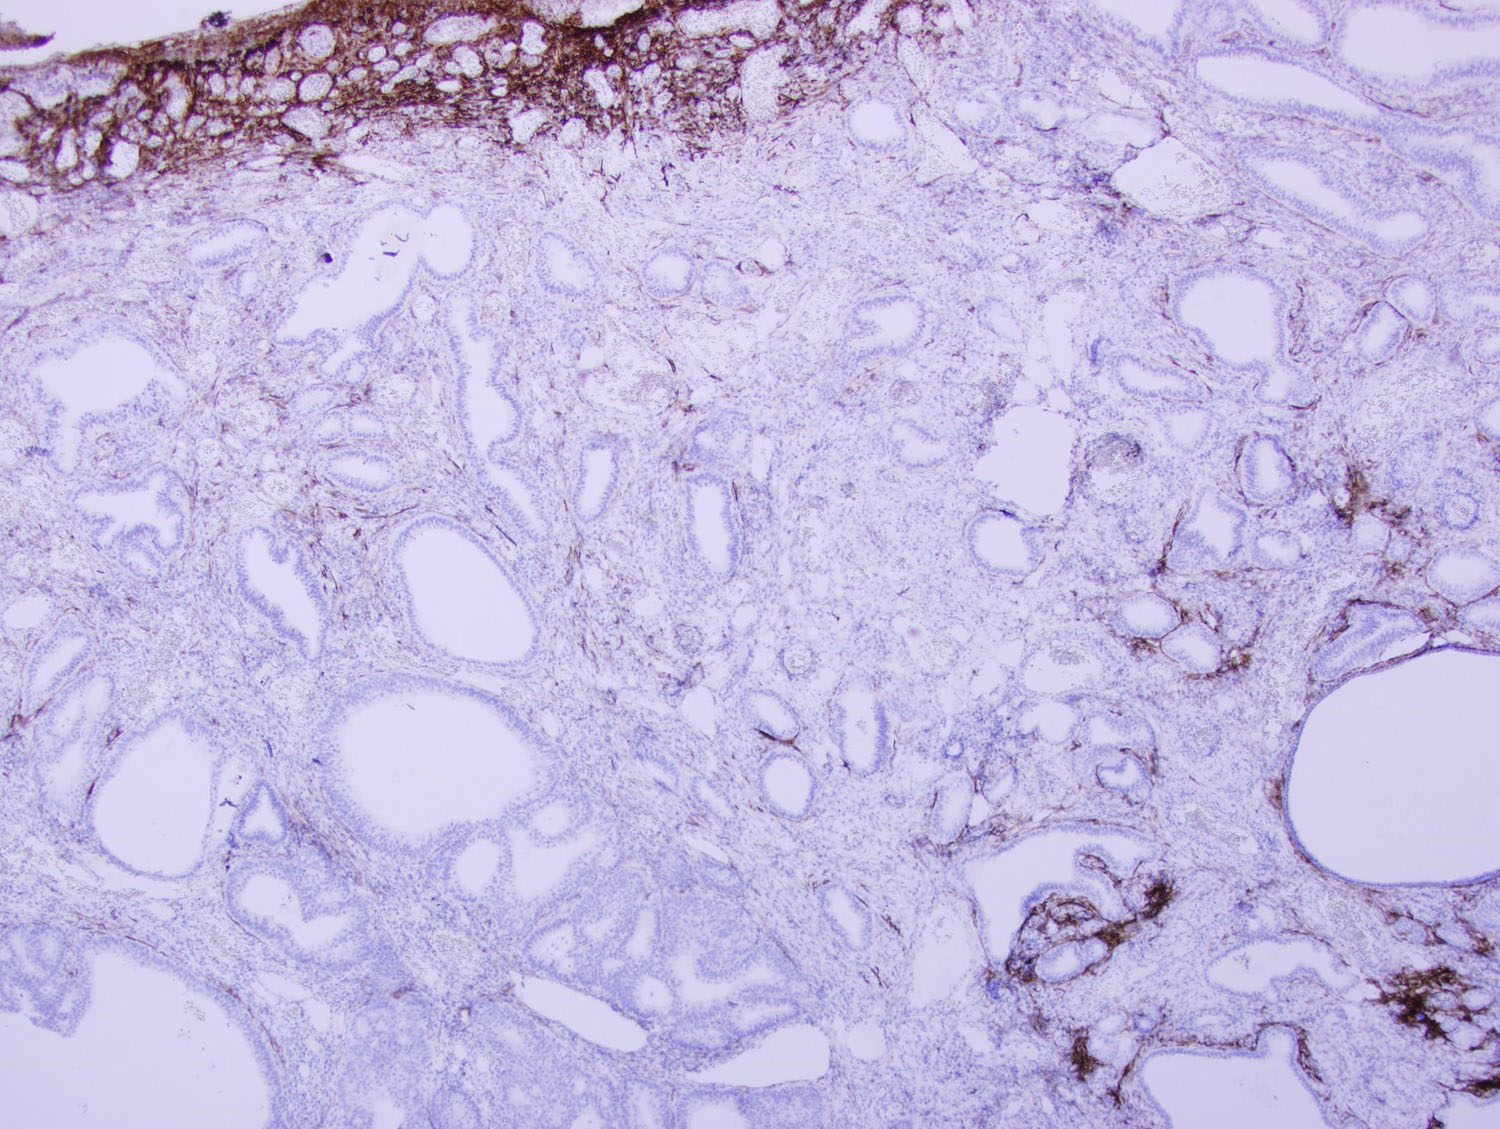

Microscopic examination of the sigmoid polyp demonstrated complete replacement of the normal colonic mucosa with infiltrating angulated and irregular glands lined by benign pseudostratified columnar epithelium, some of which were cystically dilated (Figures 2-4). Surrounding these glands was a characteristic spindle cell stroma admixed with inflammatory cells and prominently dilated vasculature. Immunohistochemical (IHC) stains were performed. The glands were negative for CDX2 and CK20 (Figures 5 and 6), while positive for PAX8 (Figure 7) and focally strongly positive for CK7 (Figure 8). The surrounding stroma was focally positive for CD10 (Figure 9).